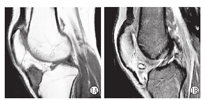

本组8例中,男5例,女3例;年龄10~17岁,平均15.1岁;左膝4例,右膝4例;病史2个月~1.5年,平均9.3个月。主要临床症状表现为膝关节反复疼痛,关节肿胀,活动受限,关节屈伸活动时疼痛明显加重,伴有不同程度的股四头肌萎缩。体检:髌下脂肪垫区压痛8例,股四头肌萎缩8例,浮髌试验阳性8例。与对侧肢体比较,膝关节均肿胀、有固定的压痛区。辅助检查:①X线片检查:8例均未见明显骨质异常表现;②MRI检查:8例均在髌下脂肪垫区有异常信号影,实性或囊实性肿物,T1W1与T2W1均呈低信号(图1);③彩色超声检查:髌下脂肪垫区异常信号影,未见明显血流信号。

所有患儿至末次复诊时,彩色超声及MRI检查(图3A、图3B)未见关节积液及复发影像表现,关节功能好(图4A、图4B、图4C)。

虽然X线片对该病的诊断无重要价值,仅能偶而发现关节肿胀、或密度增高的圆形阴影,病变侵蚀关节面时关节边缘缺损、硬化和增生。关节内受累时显示关节间隙增宽,邻近骨皮质压迫性受累。但我们还是建议常规行X线检查,以排除其他病变。MRI对于该病有极高的敏感性与特异性,表现为关节内不规则软组织肿块,呈弥漫性或浸润性生长,可明确病变的部位及范围,以及关节内受累情况。在各常规序列上,肿块均呈低信号,这是该病的影像学特征之一。其中,T1W1与T2W1均呈低信号,以T2W1影像最为明显,这是由于具有顺磁性的含铁血黄素沉着造成。如合并出血坏死,T2W1信号则较为混杂,可以为低、等或高低混杂信号。彩色超声检查可区分肿物为实性、囊实性、囊性,以及有无血流频谱,从而与髌下脂肪垫囊肿、血管瘤等相鉴别。